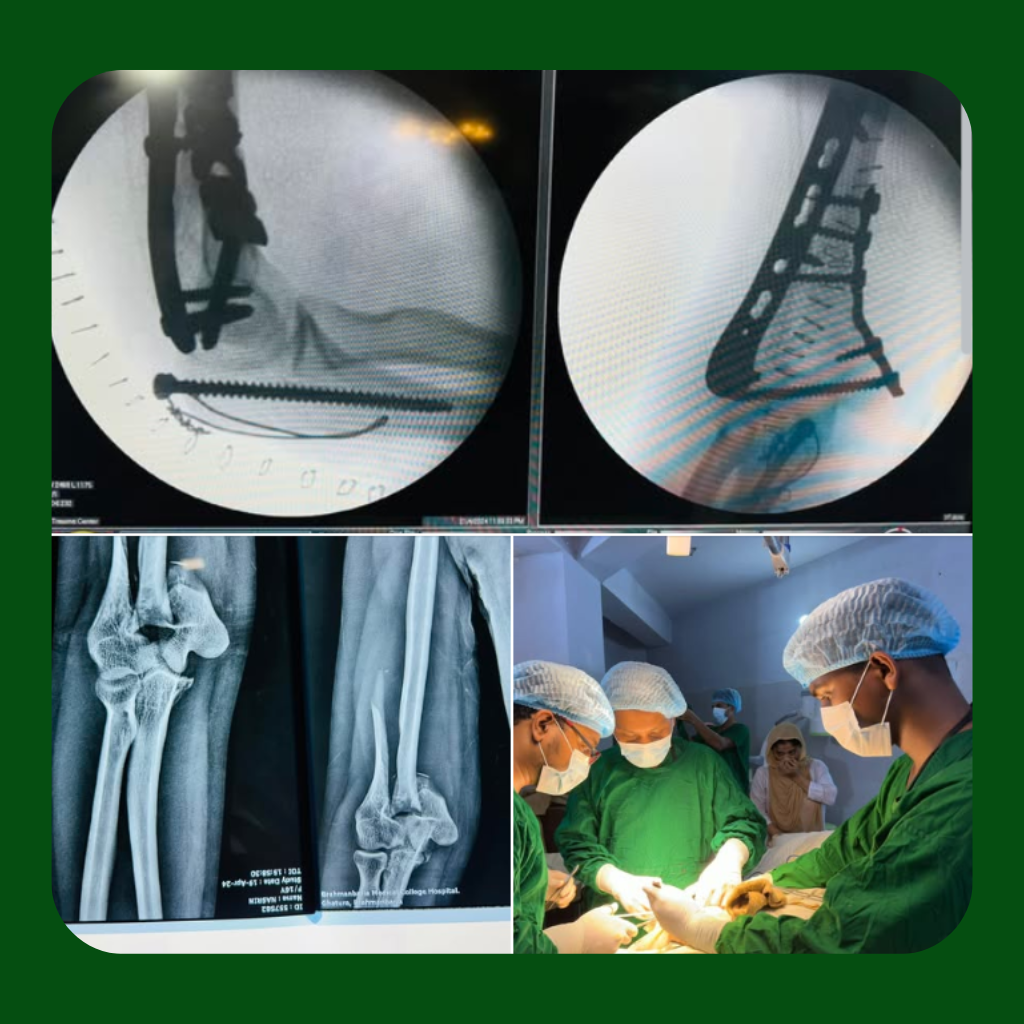

Ankle & Distal Radius Fractures

Anatomical reduction and internal fixation preserve joint congruity and minimize long-term degenerative changes following intra-articular injuries.

Distal Humerus Fracture Management

Surgical management of distal humerus fractures focuses on precise anatomical reduction of the articular surface and stable internal fixation using dual plating techniques where required. Restoration of elbow alignment and early controlled mobilization are essential to preserve joint function, prevent stiffness, and achieve durable functional recovery.